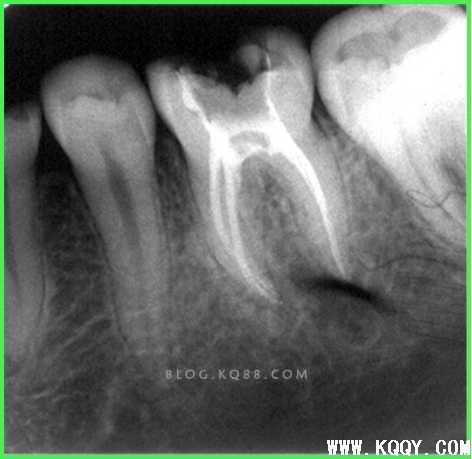

3术前认真读片,有的根管模糊是否存在多根管?还是钙化?初步了解根管的弯曲度。上橡皮障。

弯曲根管的评价:

简单根管5°-10°,中等复杂根管10°-25 ° 复杂根管大于25°。

根管测量

1.摄片确定和根测仪相结合的方式进行。